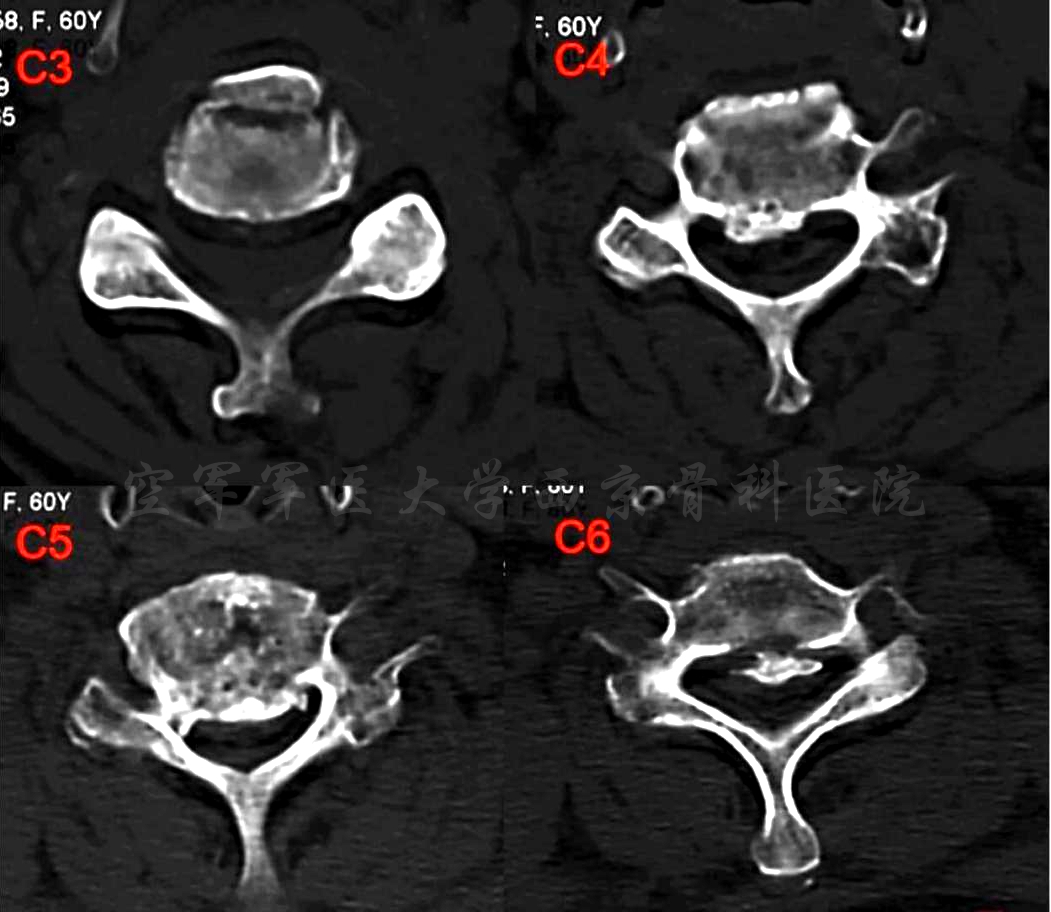

术前X线正侧位片

术前CT